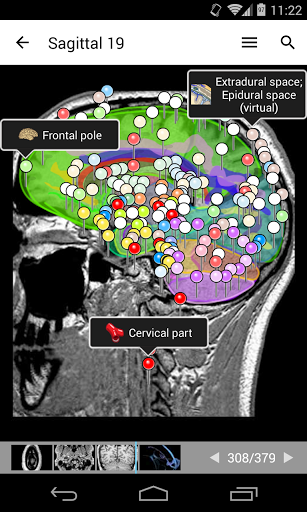

- يتميز وضع الدبابيس بسلوك جديد يسمح لك باتباع بنية تشريحية بسهولة أكبر

- يمكنك الآن تحديد حجم الخط الذي تفضله يدويًا لتسميات الهياكل التشريحية (في وضع الملصقات)

- ضمن عرض التفاصيل للبنية التشريحية ، يشير الدبوس الآن إلى البنية ذات الصلة في جميع الصور الحالية

انقر أيضًا مباشرة على الصورة للانتقال إلى الصورة المعروضة في تلك الوحدة

رسم توضيحي موجود الآن على كل صورة ويمثل الاتجاه الحالي للجسم

- عرض التشريحية يعرض الآن المزيد من التسميات

- يمكنك الآن إخفاء الهياكل واحداً تلو الآخر (زر جديد داخل نافذة الوصف المنبثقة) وعرضها مرة أخرى في القائمة الصحيحة